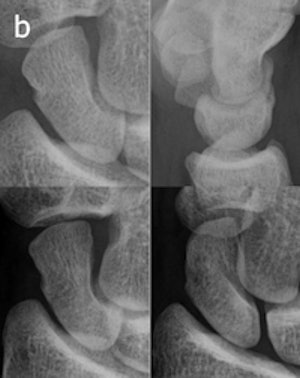

The CR protocol was identical to the previous ER imaging routine. For tomosynthesis, 60 low-dose projection images were used to reconstruct tomographic sections with 1-mm nominal thickness without overlap, with a pixel spacing of 0.2 mm. The detector was stationary, while the x-ray tube was moved continuously from -17.5° to +17.5° around the standard PA position.

The experience also taught the participating radiologists that detecting fractures with tomosynthesis is somewhat different than with conventional radiography and CT. Fracture detection is mainly based on edge disruption with tomosynthesis because the structure of the medullary bone is blurred and not as distinct as in CT, Geijer noted.

The tomosynthesis sections had a "nonprecise" thickness, with a sharp resolution at the image center, and increasing "fuzziness" apparent toward the image edges.

Fracture detection was aided on the lateral borders by the ability to visualize the scaphoid bone cortex. Fractures could also be appreciated on the most dorsal and palmar sections because of good contrast between the bone and surrounding soft tissue or medullary bone, he wrote.

Image artifacts with tomosynthesis included increased noise during scaphoid imaging and the superimposition of adjacent cortical lines and carpal joint structures.

"The way a fracture is seen with tomosynthesis is thus different from both radiography and CT," he wrote.